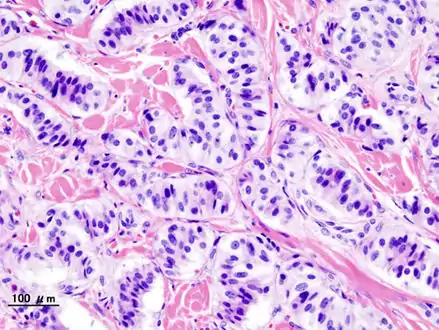

| Pathology of pancreatic endocrine tumour (insulinoma). | |